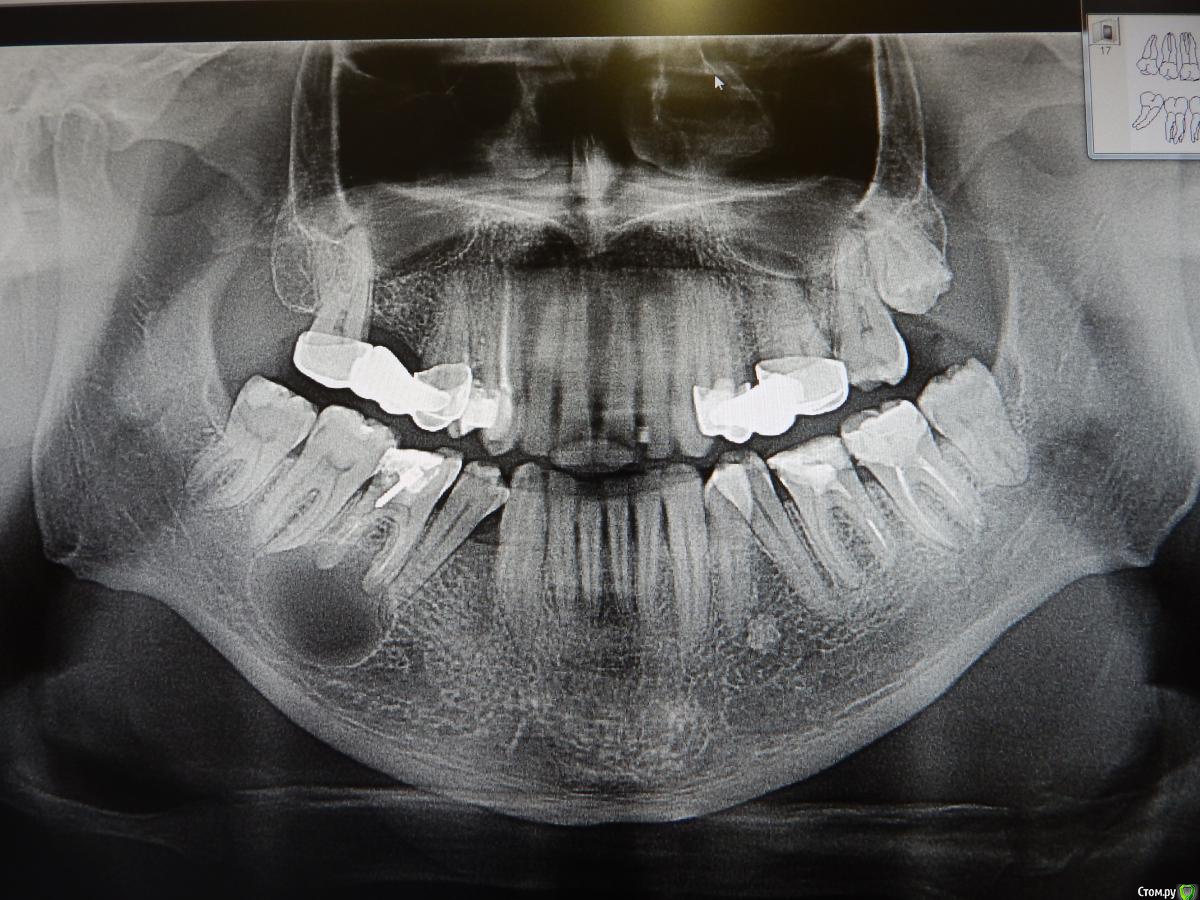

dantist_movani Опубликовано 8 октября, 2015 Поделиться Опубликовано 8 октября, 2015 Привет всем! Нужен Ваш совет! Пациент обратился с жалобой на скол пломбы 4.6 окклюзионно-лингвально, острые края режут язык. Делаю интраоральный снимок 4.6, периапикально изменения не помещаютя. Делаем ОПГ. Делаем ЭОД(4.5 и 4.7)=7-10мкА. 4.6 без обострения и со слов пациента никогда не болел, лечили более 10 лет назад. Помогите разобраться, что делать в такой клинической ситуации? Можно ли перелечить этот зуб либо необходима госпитализация пациента в ЧЛХ с последующим удалением зуба и цистотомией? Ссылка на комментарий

red_butler Опубликовано 8 октября, 2015 Поделиться Опубликовано 8 октября, 2015 Спасибо, пугают размерыразмер не имеет значения. Проверьте соседние зубы на витальность. 1 Ссылка на комментарий